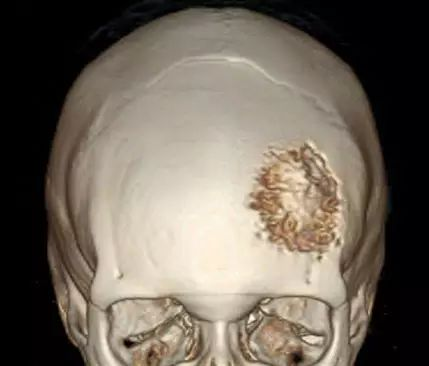

大多数脑膜瘤生长相对缓慢,具有良性肿瘤特征。国际卫生组织(WHO)将脑膜瘤分为三级。WHO I级脑膜瘤的复发风险相对较低,而更高等级脑膜瘤复发和侵袭性行为的可能性更高。WHO II级脑膜瘤为脊索状、透明细胞及非典型性病变,WHO III级脑膜瘤包括乳头状、横纹肌样和间变性肿瘤。WHO I级脑膜瘤是较常见的肿瘤,此类至少有九个亚型,较常见的是脑膜性、纤维性和过渡性脑膜瘤。下图显示的是一名61岁女性,头皮有一增大的肿块,CT扫描三维重建显示左额叶脑膜瘤累及骨质。这种影像学表现多提示肿瘤为一种侵袭性亚型。

患者前后位X线片显示左额叶透亮,表明该处脑膜瘤已经侵入骨质。(X线颅骨像很少作为初始诊断检查,其鉴别诊断范围相当广泛,包括骨肿瘤。)